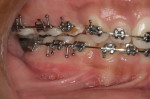

The surgical team spends much time and energy in collaboration with the orthodontist to plan the surgery.  A joint treatment plan is devised.  The orthodontist sets up for the surgery with braces.  The surgical team then plans the surgery using xrays to predict the movements, performs the surgery on models, then fabricates acrylic splints to guide the surgical team in the operating room.

After Orthodontic Setup - Presurgical